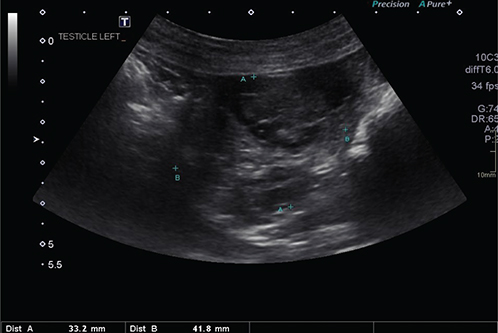

Transabdominal ultrasonography revealed an oval to globoid mass (4.2 × 3.3 cm) with irregular contour (suspected left testis), located ventro-cranially and slightly left to the urinary bladder. The mass appeared moderately cystic and heterogenous in echogenicity, with no distinct mediastinum testis (Figure 3). Mild to moderate iliac lymphadenopathy and splenic nodules were observed. Prostate measurements (35 × 32 × 40 mm) were within normal parameters for an intact dog of the patient’s size and age.7,8

Fig. 3.

Figure 3. Oblique ultrasonographic image of the irregular mass (33.2 mm between calipers A and 41.8 mm between calipers B) of suspected retained left testis (note moderate cystic and heterogenous echogenicity appearance)